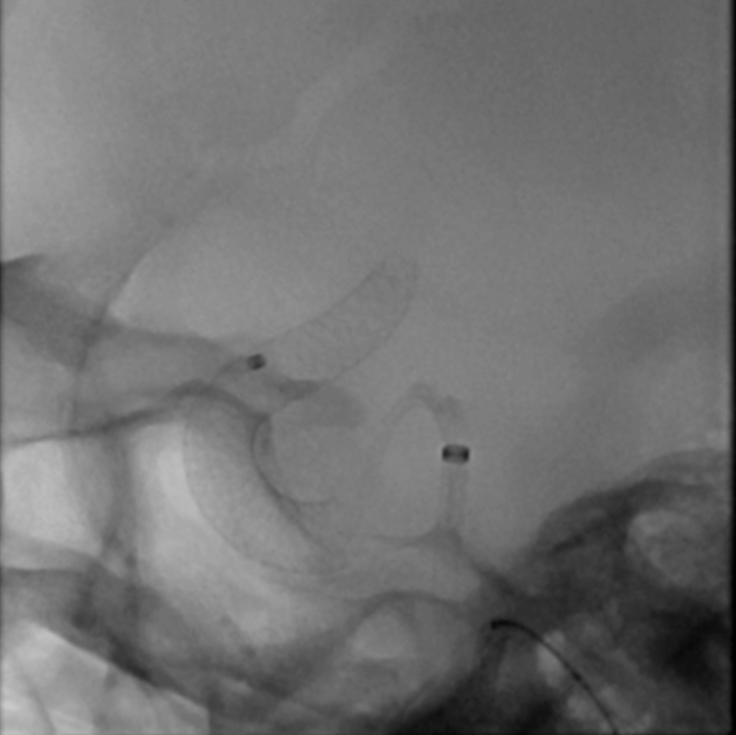

术中影像融合提示支架贴壁良好

眼动脉,脉络膜前动脉,后交通动脉血流无影响